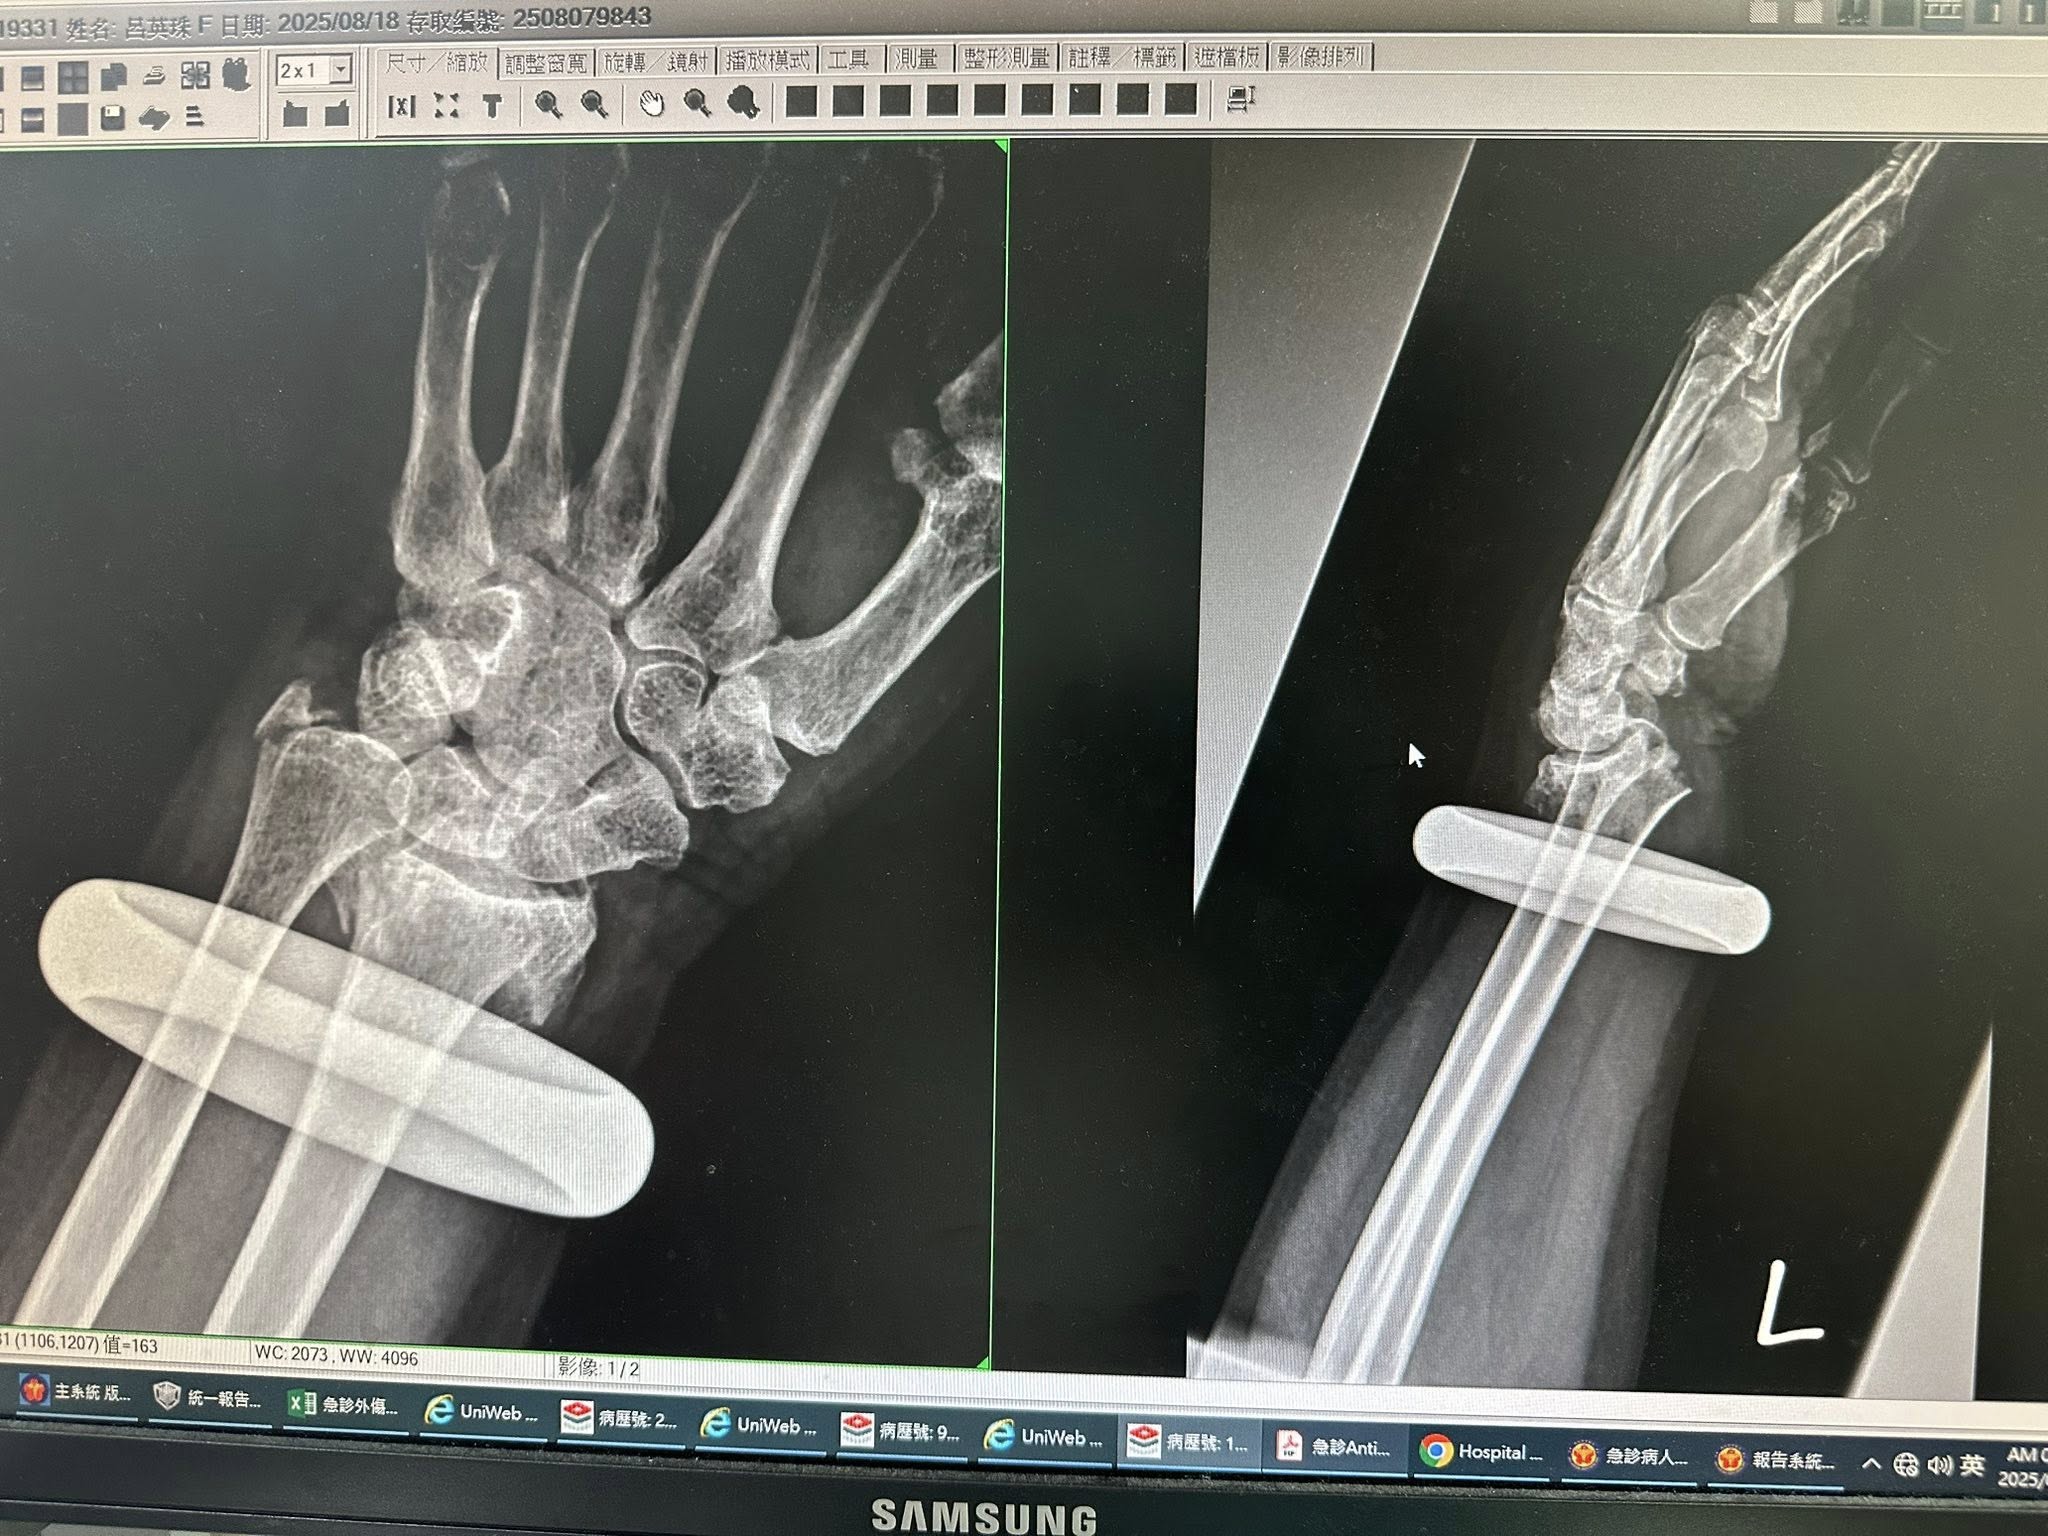

根據《三立新聞》報導,這起意外發生在18日凌晨,當時兵家綺才剛服用安眠藥不到30分鐘,就接獲緊急通知,指出她的媽媽不慎摔倒,「失智老人最不可控的就是半夜起床摔倒,這一摔就骨折+粉碎性骨折!」

在急診室等待的過程中,兵家綺忍受著藥物帶來的昏沉感,還要面對環境的低溫。而母親配戴多年的玉鐲也必須破壞拆除,才能進行後續治療,這一連串突發狀況,讓她身心俱疲。